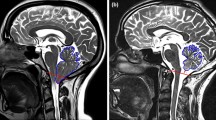

Chiari malformation (CM-I)

Three studies compared displacement of specific brain regions in patients and/or healthy controls using a “pixel-shifting” method to track motion of anatomical landmarks in images acquired using cardiac-gated cine balanced steady-state gradient echo sequences (sagittal plane 2D FIESTA or bFFE) [8, 27, 28]. One study used phase-based aMRI to qualitatively compare brain motion in one CM-I patient to one control subject [5].

Overall, three studies showed tonsillar motion is greater in CM-I patients compared to controls subjects (Fig. 5); these studies identified an increase in magnitude of downward caudal midbrain tissue displacement at the level of the brainstem and cranio-cervical junction in CM-1 patients [5]. This could be due to the additional pressure exerted by the CM on the spinal cord leading to an abrupt downward displacement of the spinal cord during systole, which impairs the return of CSF to the cranial cavity.

Table 2 compares data from CM-I patients and healthy controls. Larger BTPs are consistently observed in CM-I, especially in the cerebellum tonsillar region, where pooled analysis of data from CM-I patients and healthy participants (in 3 studies) suggested motion was 0.31 mm [95% CI: 0.23, 0.38, p < 0.0001] higher in CM-I patients compared to controls (Fig. 5) [8, 27, 28]. See Supplementary Appendix. 5 for more details of data included in this pooled analysis.

CM-I studies confirmed that brain tissue motion is affected by the presence of disease, which can be investigated quantitatively using MRI cardiac-gated cine bSSFP sequences. Anatomical landmark motion tracking can then be used to measure displacements through the evaluation of pixel-shifting between frames. Such tracking of bSSFP images could provide an appropriate quantitative method to investigate brain motion in CM patients, due to its sensitivity to cephalad and caudad cerebellar tonsil motion. This method also achieves good SNR and is able to analyse contiguous blocks of data, however, standard cine bSSFP is not very sensitive to sub-voxel motion and therefore may not be as sensitive as DENSE, PC and aMRI to differences in BTP. The aMRI method also appears promising for visualising brain tissue motion in CM patients. Further studies are needed to develop aMRI for quantitative tissue motion measurements, which could potentially be achieved by using a phase-contrast MRI sequence for determining velocities and aMRI to amplify the tissue movements.